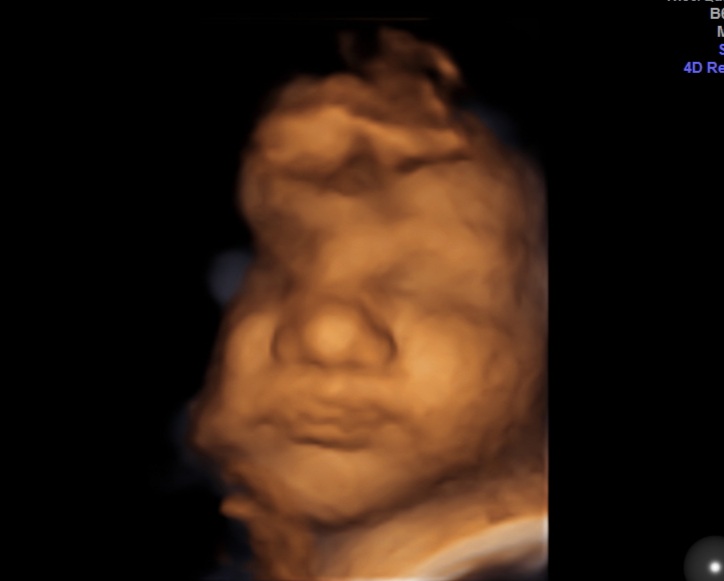

Ещё сегодня ходили на заключительное 3д узи. Такой красивый детеныш у нас получился все таки☺

В конце, по традиции, скорчил очень смешную рожу, мы с мужем и врачом так смеялись, а я до сих пор без смеха не могу смотреть, думаю даже распечатать это фото😂

Показатели все отличные, всё ещё обгоняет срок на неделю по месячным и на 2 по овуляции.

Вес примерно 2800🐹)) Кстати, сколько вашим детям на этом сроке ставили и сколько в итоге они родились?)